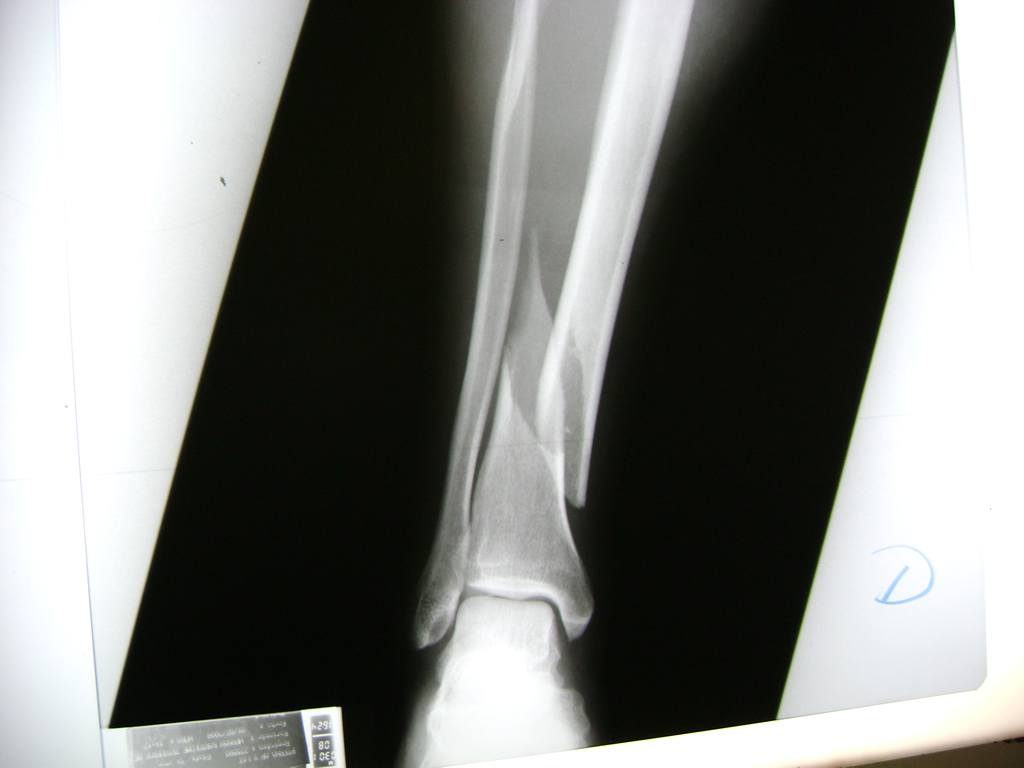

Aunque cada uno de estos huesos puede fracturarse por separado, normalmente la rotura es una lesión que se produce de forma conjunta

La mayor parte de las roturas implican a la parte proximal del hueso (parte del hueso próximo a la rodilla) o a la parte distal (parte del hueso cerca del tobillo).

Debido a la fina cobertura de piel que recubre la tibia y el peroné, las fracturas generalmente son abiertas, es decir, el hueso roto rasga la piel, atravesándola. Las fracturas de tibia y peroné generalmente se producen por un fuerte impacto o torsión.